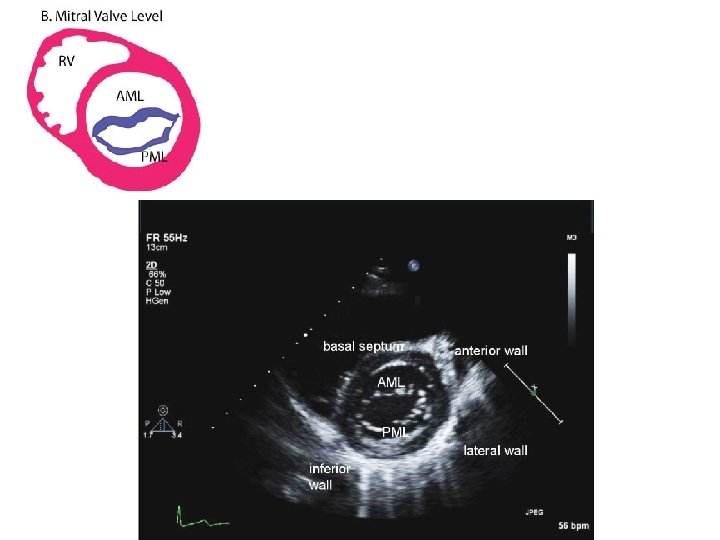

PARASTERNAL SHORT AXIS